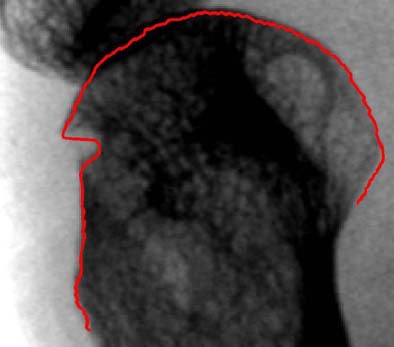

| The yellow dashed line indicates first approximation of the bone contour by an active shape model (ASM), "ignoring" everything that does not fit into the ASM, which has been trained only on intact bones. The line with red dots indicates the "ASM-driven snake" result. A more flexible search is started from the first ASM approximation (dashed line) and adapts also to erosions and fine structure on the bone contour. All images courtesy of Dr. Philipp Peloschek. |

"The 'ASM-driven snakes' algorithm is based on an initialization by active shape models (ASM)," Peloschek explained in an e-mail to AuntMinnie.com. "These models … contain ‘knowledge’ about the variability of bone shapes. Thereby they are able to detect the bone contour with high robustness and reasonable accuracy."

Another step is needed to deal with anatomical variation and pathological deformations of bones, Peloschek said, meaning that the ASM results can be used only as a rough first approximation. The additional precision is obtained with initialization of a "snake algorithm" (aka the "rubber band"), which moves about more freely than the ASM throughout the image domain.

By controlling parameters such as the elasticity and rigidity of the snake, the snake algorithm adapts the bone-contour estimate to the real bone boundary, even in areas where the bone contour has been affected by rheumatoid arthritis. Still, the snake algorithm is a work-in-progress. There are no erosions in the normative dataset, so these variations cannot be modeled by the ASM, he said.